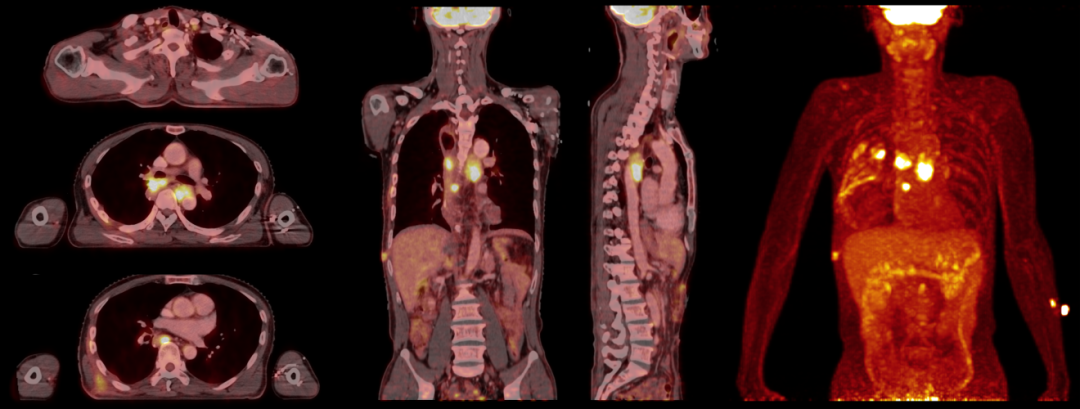

下述病例為食管非角化型鱗狀細胞癌術后1月余,患者為求進一步診治,于中南醫院核醫學科Biograph mCT設備上行18F-FDG PET/CT放療定位掃描

PET/CT圖像顯示左側鎖骨上區、右肺門、降主動脈右前方、T8椎體前方、右側第6后肋旁多發腫大淋巴結,代謝異常增高,考慮轉移性病變。

患者有放化療指征,無明顯放化療禁忌,腫瘤放化療科依據PET/CT放療定位圖像精準勾畫靶區后行縱隔放療(Dt=50.4Gy/28F) ,同時行兩周期DF方案同步化療(氟尿嘧啶+順鉑)。

放療術后兩月行18F-FDG PET/CT復查,復查圖像顯示全身未見明顯FDG代謝異常增高,腫瘤糖酵解總量(TLG)由157.30降為0,提示完全代謝緩解。